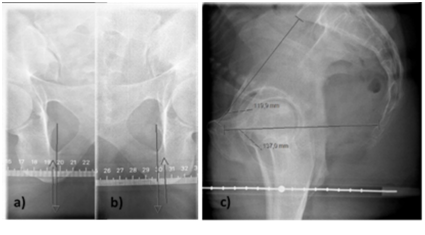

Three images were taken using the phantom. The images corresponded to the on-site conventional X-ray pelvimetry. Anteroposterior (AP) views of the left and the right sides of spina ischiadica (Figure 2a & Figure 2b) were taken, using 60kilovolt (kV) and 20 milliampere seconds (mAs). The angle of the X-ray tube was 22 degrees in the caudal direction.18 The focus to detector distance was 125cm and the collimation was set to 7cm width and 18cm length. The top of the collimation was 3cm from the upper edge of the symphysis. One lateral view was taken (Figure 2c) viewing the sacrum and symphysis using 90kV and 64mAs.3,19 Collimation was set to 26cm width and 24cm length and centred in height with symphysis and laterally over the trochanter major. Five exposures were executed for each view during the pelvimetry performed using conventional radiography to increase the reliability of the measurement. Thus, the result of the reading for each TLD was divided by 5 prior to additional calculations that are further described in the analysis section.

Figure 2 Pelvimetry performed using conventional radiography included with measurement points. Frontal projection (a, b) imaging the measurement points of the ischial spine and ischial tuberosity. The lateral projection (c) imaging the inlet and outlet diameters of the pelvis together with a lead ruler for correction of magnification/minification, placed between the women’s thighs.